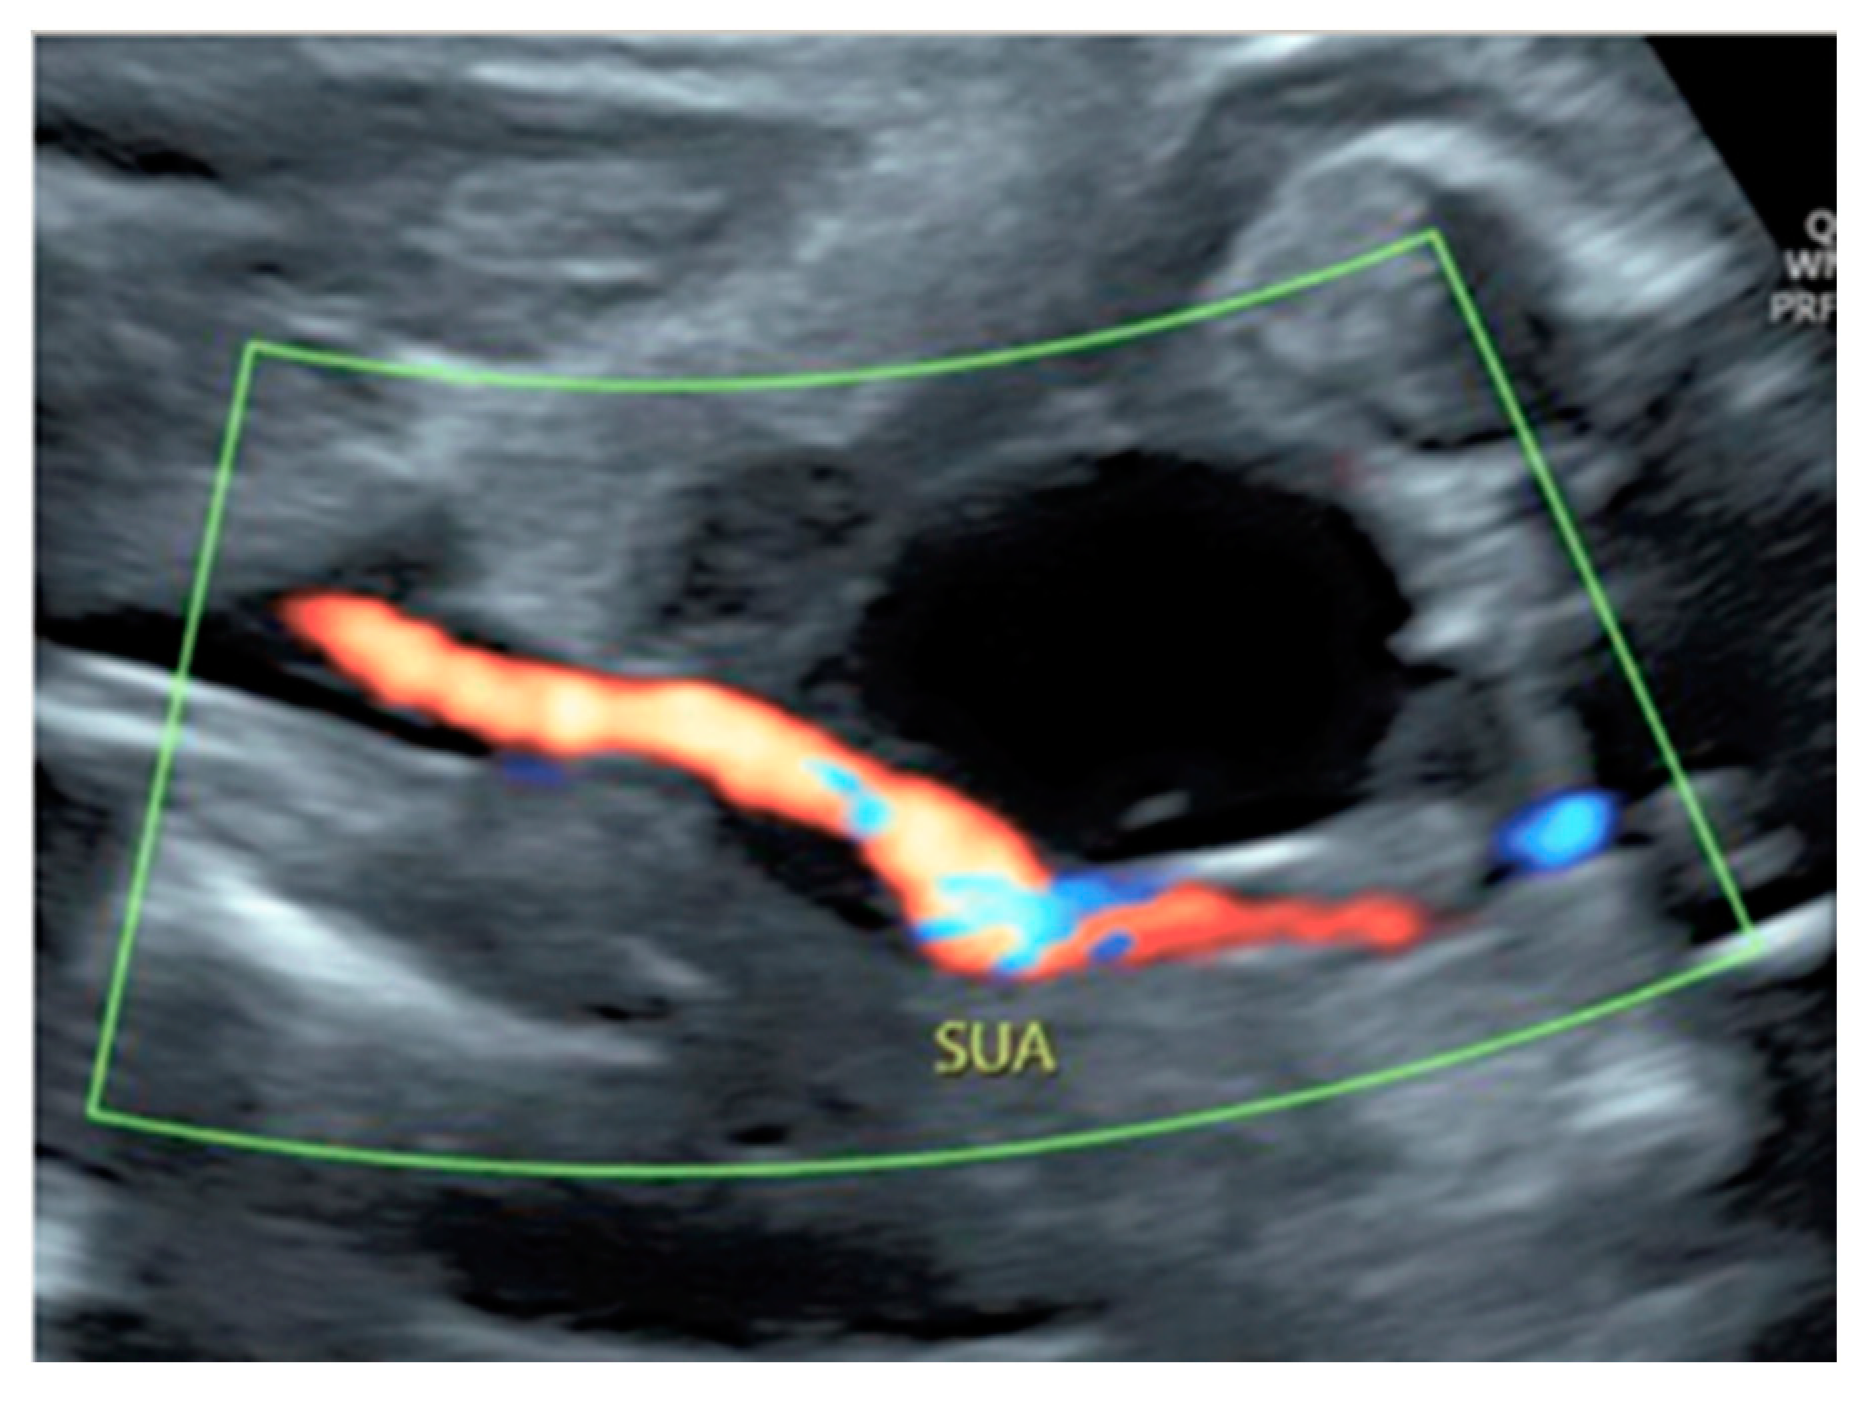

3.2.10. Single Umbilical Artery

A single umbilical artery (SUA) has a prevalence of 1.0% of all pregnancies, with greater frequency of an absent left umbilical artery than absent right umbilical artery [47]. Fetuses with isolated SUA have a general favorable in utero prognosis while those with other associated congenital anomalies are at higher risk of chromosomal abnormalities, pregnancy complication, mortality and morbidity in the neonatal period [47,66,67]. Sonographic diagnosis can be made on an axial view of the umbilical cord, with only two vessels seen on grey-scale, or by visualizing only one artery next to the bladder on the fetal pelvis using color Doppler ultrasound [47] (Figure 30 and Figure 31).

Figure 30.

Doppler ultrasound showing a single umbilical artery (SUA) coursing along the bladder.